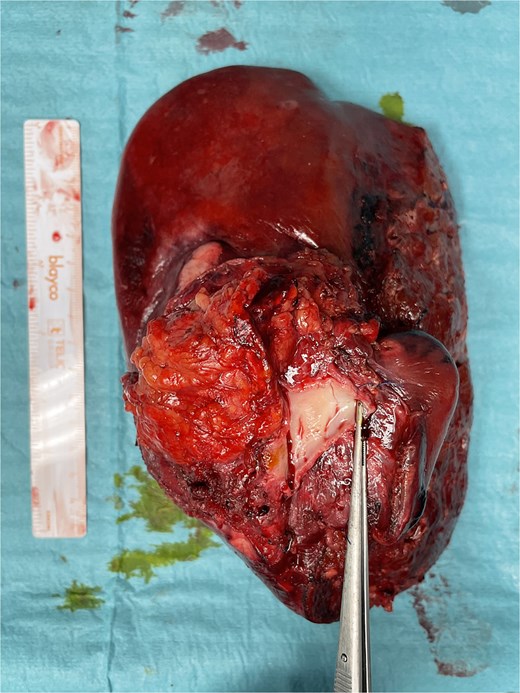

Final specimen. The resected specimen shows intrahepatic cholangiocarcinoma with invasion of the IVC.

The post-operative period was complicated by bleeding from the left epigastric artery at the APFP harvesting site on post-operative day 14, requiring reintervention and vessel ligation. The patient was discharged on post-operative day 31. Pathology confirmed an ypT4G2N1R0 small-duct intrahepatic cholangiocarcinoma. No post-operative thrombosis or clinically significant stenosis were identified. Figure 6 demonstrates the reconstructed vessels 1 year after surgery. After completing 6 weeks of therapeutic low-molecular-weight heparin (LMWH), the patient continued rivaroxaban 20 mg once daily.